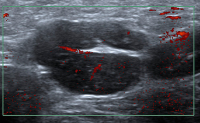

Ultraschall-Lymphknoten

Abbildung 1: Normalbefund zervikal. Diesen kennzeichnet eine scharfe Begrenzung, ein echoreicher Hilus, eine gleichmäßige Breite des Kortex, eine reguläre Größe und ovale Form.